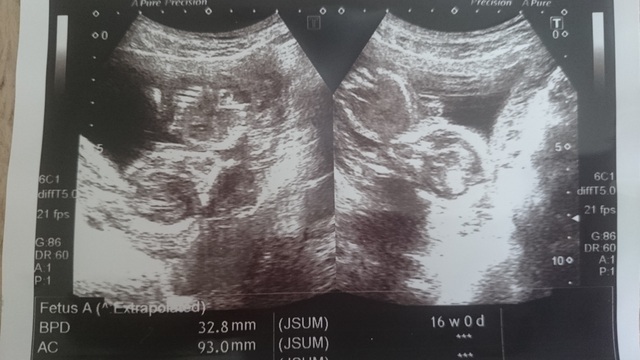

16週0日(16w0d・男の子)|ゆきあママ さん(20歳)

エコー写真撮影時のエピソード:

中々婦人科に行けなくて久しぶりに行った時に徐々に人間らしくなってきて本当にうれしかったです!

前に辛い思いをしてたのですくすくお腹の中で成長して行ってくれてることが何よりも安心でした 旦那も喜んでました。